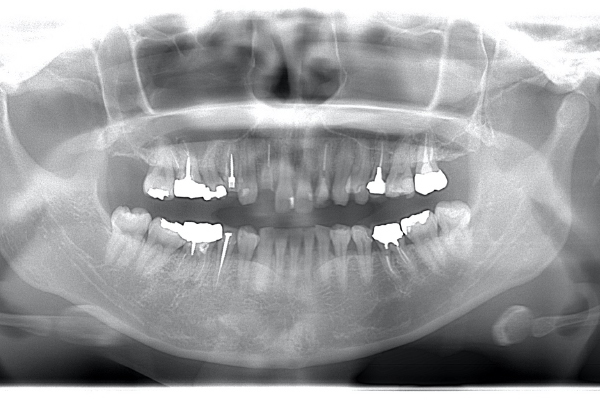

レントゲンで見ても、右上2では歯質が歯肉縁上にのこっていない。しかし歯根は長いのでMTMの適応症例です。

| 治療前 | 治療後 |

|---|---|

![]() |

| 治療前で歯根が長いのがわかります。歯根がある程度長く無いと、MTMは行えません。 | MTM終了時のもの。フックが上の金属に接している。また根尖に透過像があるが、歯が動いた証拠です。 |